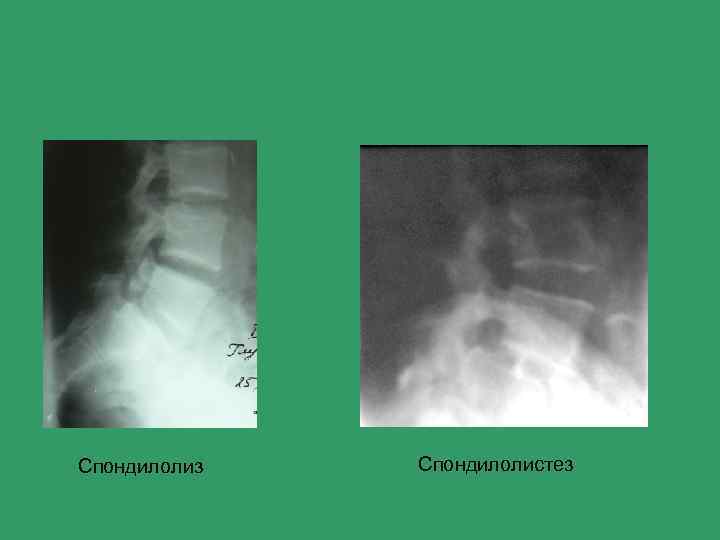

Болевой синдром в поясничной области Основные причины 1) Пиелонефрит, гломерулонефрит 2) Почечная колика 3) Дисплазии позвоночника 4) Остеохондроз 5) Остеопороз I и II типа 6) Спондилолиз, спондилолистез 7) Лигаментоз, тендиноз пояснично-крестцового отдела 8) Синдром Кюммеля 9) Сакроилеит 10) Метастазы в кости позвоночника

Алгоритм лучевого обследования при болевом синдроме в поясничной области • Уровень I Рентгенография в 2 -х проекциях Нет изменений Есть изменения Функциональные снимки Уровень II МРТ

Спондилолиз Спондилолистез